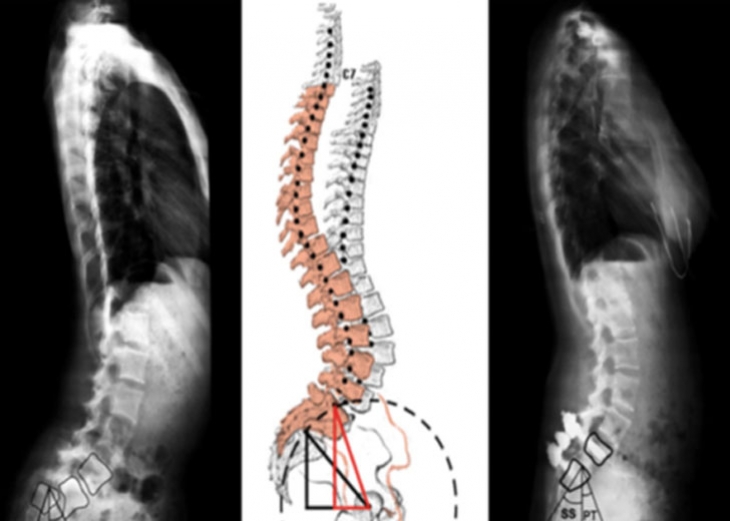

引 言腰椎重度滑脱症定义是指椎体滑移率>50%,Meyerding>II度。青少年人群中发病率为2.4%,常累及L5/S1节段。发育,创伤,手术和病理是造成腰椎重度滑脱症的因素。依据SDSG分类...